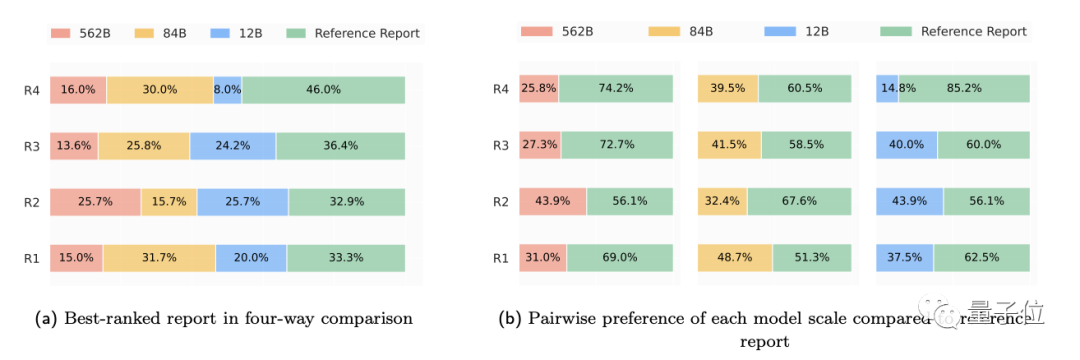

而在246份真实胸部X光片中,临床医生表示,在高达40.50%的病例中,Med-PaLM M生成的报告都要比专业放射科医生的更受采纳,这表明Med-PaLM M并非“纸上谈兵”,用于临床指日可待。

性能评估阶段,作者主要测试Med-PaLM M的“多面手”(即全科)能力、突发涌现能力以及放射学报告生成质量(与真实放射科医生进行对比)。

(2)在scale实验中,三个不同规模的Med-PaLM M对各类任务的影响各不相同:

粗略来看,对于纯语言任务和需要调整的多模式任务来说,模型越大越好;但对图像分类和胸部X光报告生成任务来说,84B的效果比562B表现反而更好一些。

(4)放射性报告生成测试中,80B参数的Med-PaLM M平均有40.50%的报告比放射科医生做的更好(被临床医生采纳),而12B和562B,分别为34.05%和32.00%。

另外,遗漏和错误率测试显示,Med-PaLM M 12B和84B模型平均每份报告的遗漏率最低,为0.12,其次是562B模型为0.13。这一结果与MIMIC-CXR上人类放射科医生基线报告的相当。